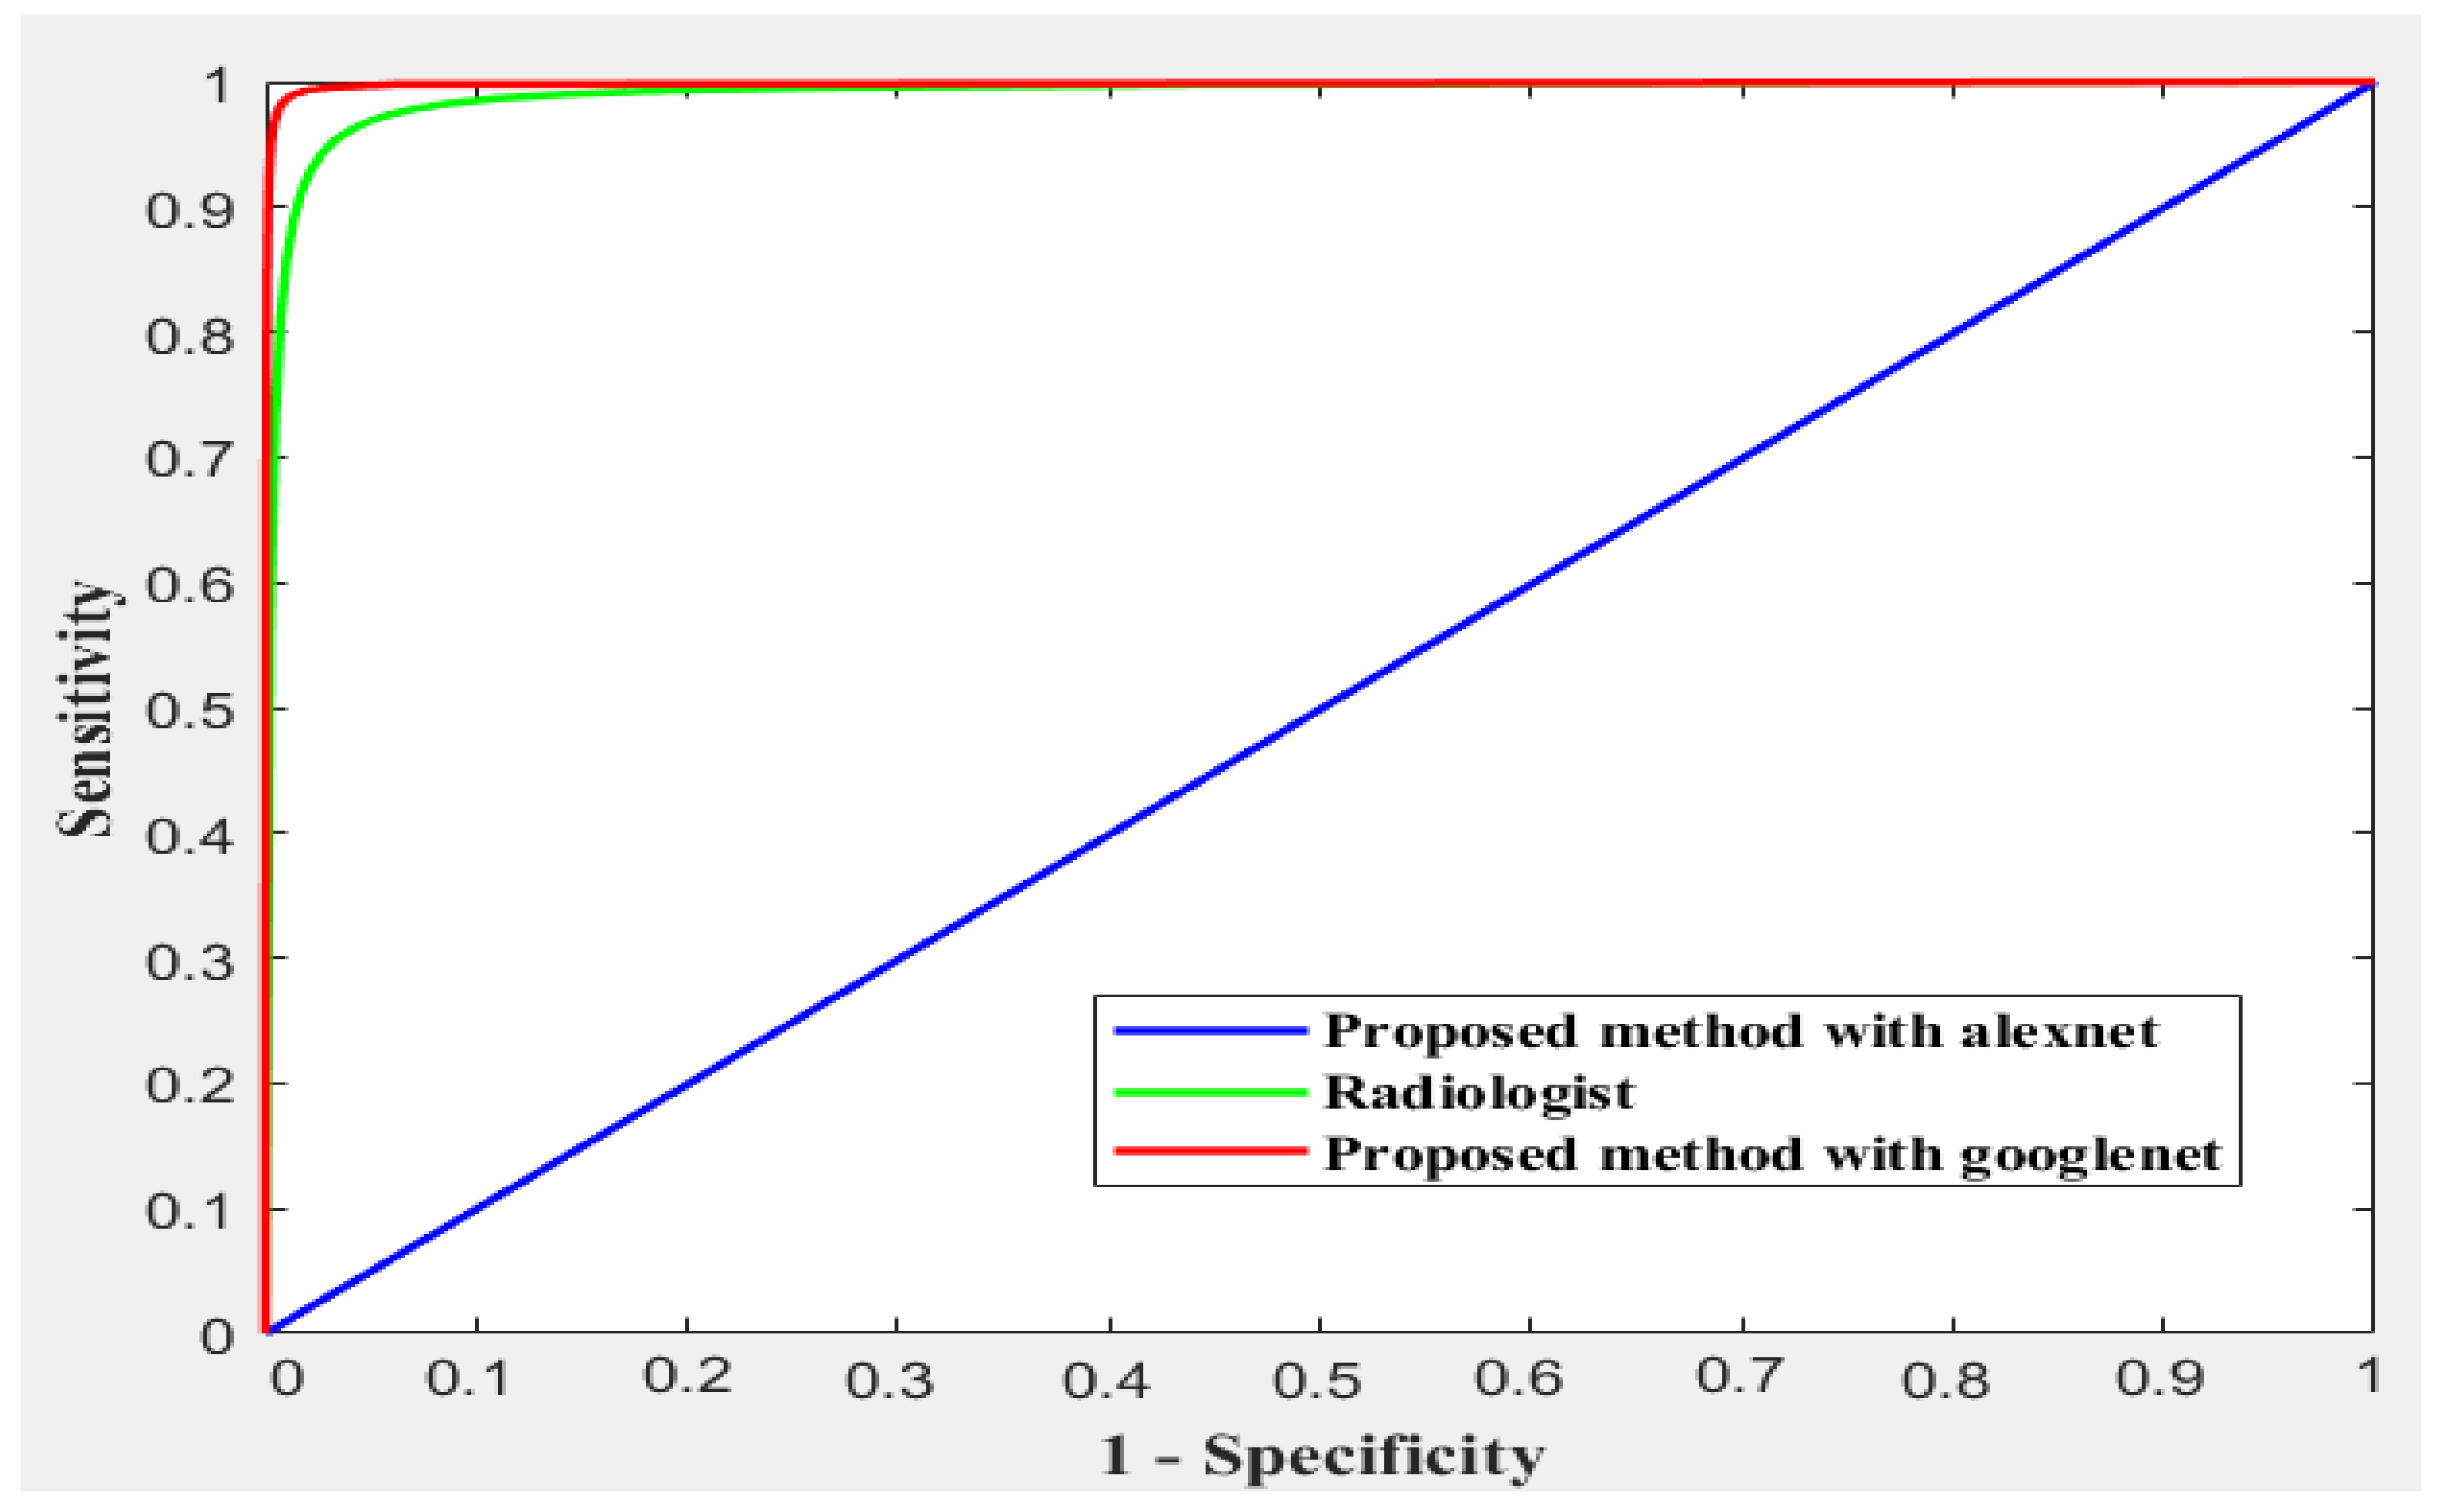

4.1.1. Comparative Study

| Accuracy | Sensitivity | Specificity | Precision | F1-Score | |

|---|---|---|---|---|---|

| Radiologist | 95% | 93% | 96% | 87% | |

| The proposed method with AlexNet | 59.2 | 33.33 | 66.67 | 13.0 | 18.67 |

| The proposed method with GoogleNet | 99.55% | 99.33% | 99.66% | 99.33% | 99.67 |